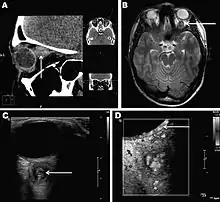

Infections in humans[2] usually manifest as a single subcutaneous nodule, which is caused by a macrofilaria that is trapped by the immune system. Subcutaneous migration of the worm may result in local swellings with changing localization. In addition, rare cases of organ manifestation have been reported, affecting the lung, male genitals, female breast, or the eye. The latter is found in particular during the migratory phase of the parasite. D. repens occurs more commonly in adults (aged 40–49 years). The only exception is in Sri Lanka, where children younger than nine years are most likely to be infected. The youngest individual reported was aged four months.[3]

Final diagnosis is established by microscopic examination of the excised worm. Making a definite species diagnosis on morphologic grounds is difficult, because a large number of zoonotic Dirofilaria species have been described that share morphologic features with D. repens.